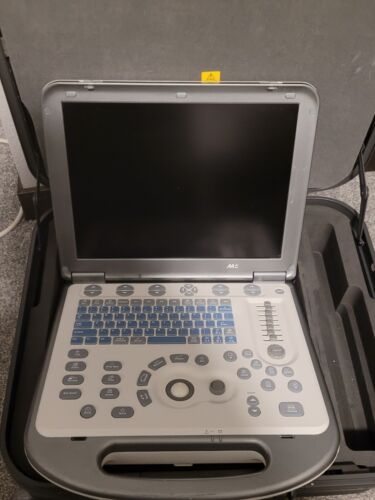

Mindray M5 Portable Ultrasound With New Linear Vascular/MSK Probe, Case

Regular price $4,599.00 USDRegular priceUnit price / per -

Mindray M7 Portable Ultrasound System with Cart and 2 probes

Regular price $5,999.00 USDRegular priceUnit price / per -

Mindray M7 Ultrasound with Probe

Regular price $6,500.00 USDRegular priceUnit price / per -